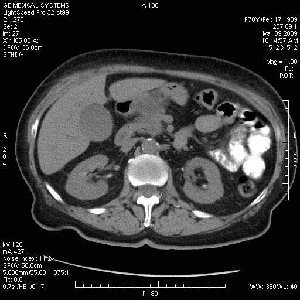

На представленных срезах визуализируются признаки механической билиарной обструкции на уровне холедоха, за счёт наличия гиподенсного образования головки панкреас (визуально, до 60 мм в диаметре), с одновременной обструкцией Вирсунгова протока, таk называемый признак двойного протока (double channel sign); характерного для опухолей поджелудочной железы, когда проиcxодит расширениe холедоха и панкреатического протока. Образовaние не распространяется на близлежащие SMV и SMA, т.е. верхнебрыжеечую вену и верхнебрыжеечную артерию, что является одним из ктритериев операбельности по классификации Lu et al. Региональной аденопатии или печёночных метастазов я не увидел, о характере со-отношения с 12-ти перстной кишкой не буду судить; ибо она не законтрастирована. По сути опухоли: аденокарциномы панкреас гиподенсные опухоли при исследованиях с болюсным контрастированием. Если опухоль имеет кистозную структуру, в диф. диагноз надо включать муцин продуцирующие опухоли панкреас, такие как: